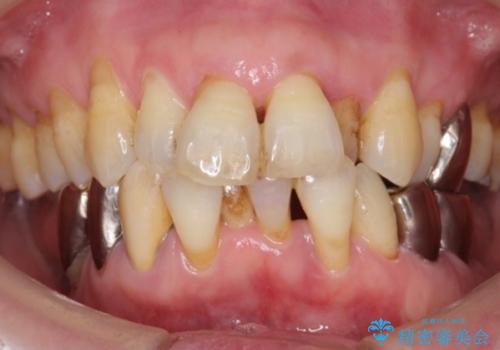

- 下の前歯(左下2)と奥歯の動揺がひどくなってきたことを主訴に来院された患者様です。

精査したところ、前歯の咬み合わせが反対になっていること、下の奥歯(下顎両側67)が4本欠損していることから動揺が生じていました。

矯正治療やインプラント・再生療法を併用した全顎的な治療を提案させて頂いたところ、予算を抑えて早く治したいとのことでご希望されませんでした。

- ¥1,110,000 (根管治療×1本、土台×2本、仮歯×9本、クラウン×9本)費用は治療当時の料金となります